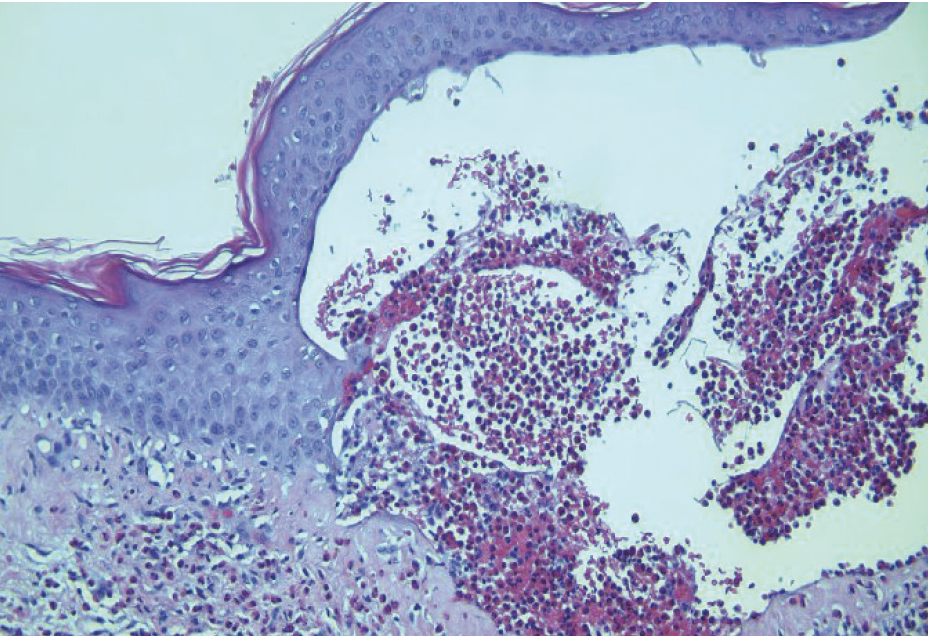

The patient’s diagnosis of localized BP was confirmed with H&E stain and DIF histopathology, which revealed eosinophil-rich subepidermal blistering and a linear deposition of IgG and C3 along the basement membrane, respectively (Figures 2–4). Serology was also positive for BP180 antibodies. The patient was prescribed topical clobetasol propionate 5% cream, which led to significant improvement in his pruritus and bullae. He denied systemic therapy and is being closely monitored. To date, the patient has not experienced any recurrence or disease progression.

Histopathology will reveal a clean split at the dermoepidermal junction and formation of a subepidermal blister with eosinophils. Direct immunofluorescence (DIF) is considered the gold standard for diagnosis and will reveal linear IgG and/or C3 at the basement membrane in nearly 100% of cases. Serologic workup will be positive for autoantibodies against BP180 or BP230.2